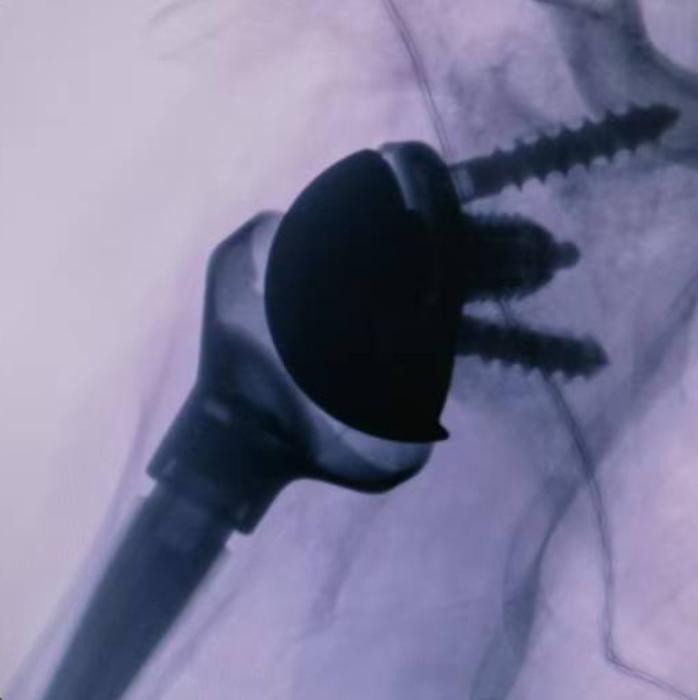

关节与运动医学科陶崎峰主任医师组织多学科讨论,建议患者接受右反式人工肩关节置换术。手术由王洋主刀、刘浩、李胜发医生联合完成,过程顺利,假体位置良好,术后疼痛明显减轻,肩关节活动度逐步恢复。此次手术的成功再次体现了医院在复杂肩关节疾病治疗及人工肩关节置换领域的专业实力。(吴平华 李胜发 刘浩 供稿)